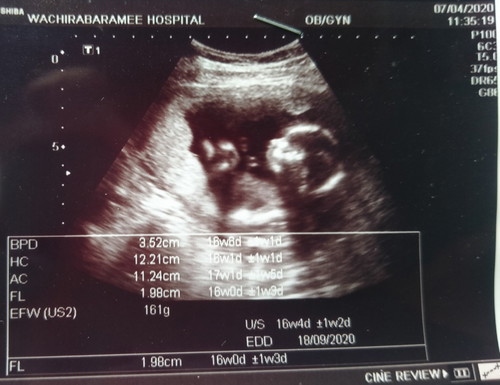

ฝากครรภ์กำหนดคลอด 20 ก.ย. 63 อัลตร้าซาวด์กำหนดคลอด 18 ก.ย. 63 คุยกับลูกชายแล้วว่าแม่ขอคลอดน้องเองเพื่อประหยัดแล้วก็สะดวกในระยะทาง ยอมรับแล้วว่าโดนทิ้งติดต่อไม่ได้ตั้งแต่คืนวันที่ 12 ก.พ. 63 อยู่บ้านตัวเองไม่ได้ทำงาน เงินเยียวยาก็ไม่ได้ ไม่มีใครเลี้ยงดูส่งเสีย ท้องหางานทำก็ไม่เอา อยู่กับลูกชาย 11 ขวบ แล้วก็ลูกในท้อง ทนๆไปก่อนนะลูกคลอดน้องก่อน ปลายปี 63 เราสามคนแม่ลูกเริ่มต้นชีวิตใหม่กัน